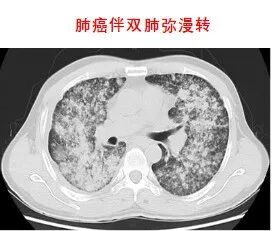

3.分子靶向治疗

靶向治疗,是在细胞分子水平,针对已经明确的致癌位点(该位点可以是肿瘤细胞内部的一个蛋白分子,也可以是一个基因片段的突变)进行靶向抗肿瘤治疗。分子靶向治疗具有特异性抗肿瘤作用,使肿瘤细胞特异性死亡,不会波及肿瘤周围的正常组织,其疗效增加,毒副作用明显减少。